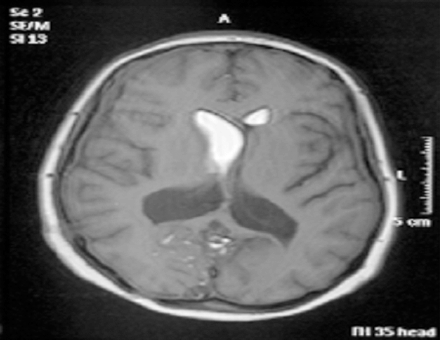

As usual, the patient recovered rapidly to GCS 15, headache free, but this time when she was mobilized after a couple of days in bed there was no deterioration and she managed to progress to the regional rehabilitation hospital and eventually to independent life in the community. She has currently been followed up for six years with no further shunt malfunctions and imaging showing normal ventricular size, complete evacuation of the lipid from the right lateral ventricle and no recurrence of the posterior fossa dermoid cyst (Figures 2,3).

Click below to enlarge

Figure 2: Axial T1-weighted MRI scan showing intraventricular fat in both lateral ventricles and in the cortical sulci..